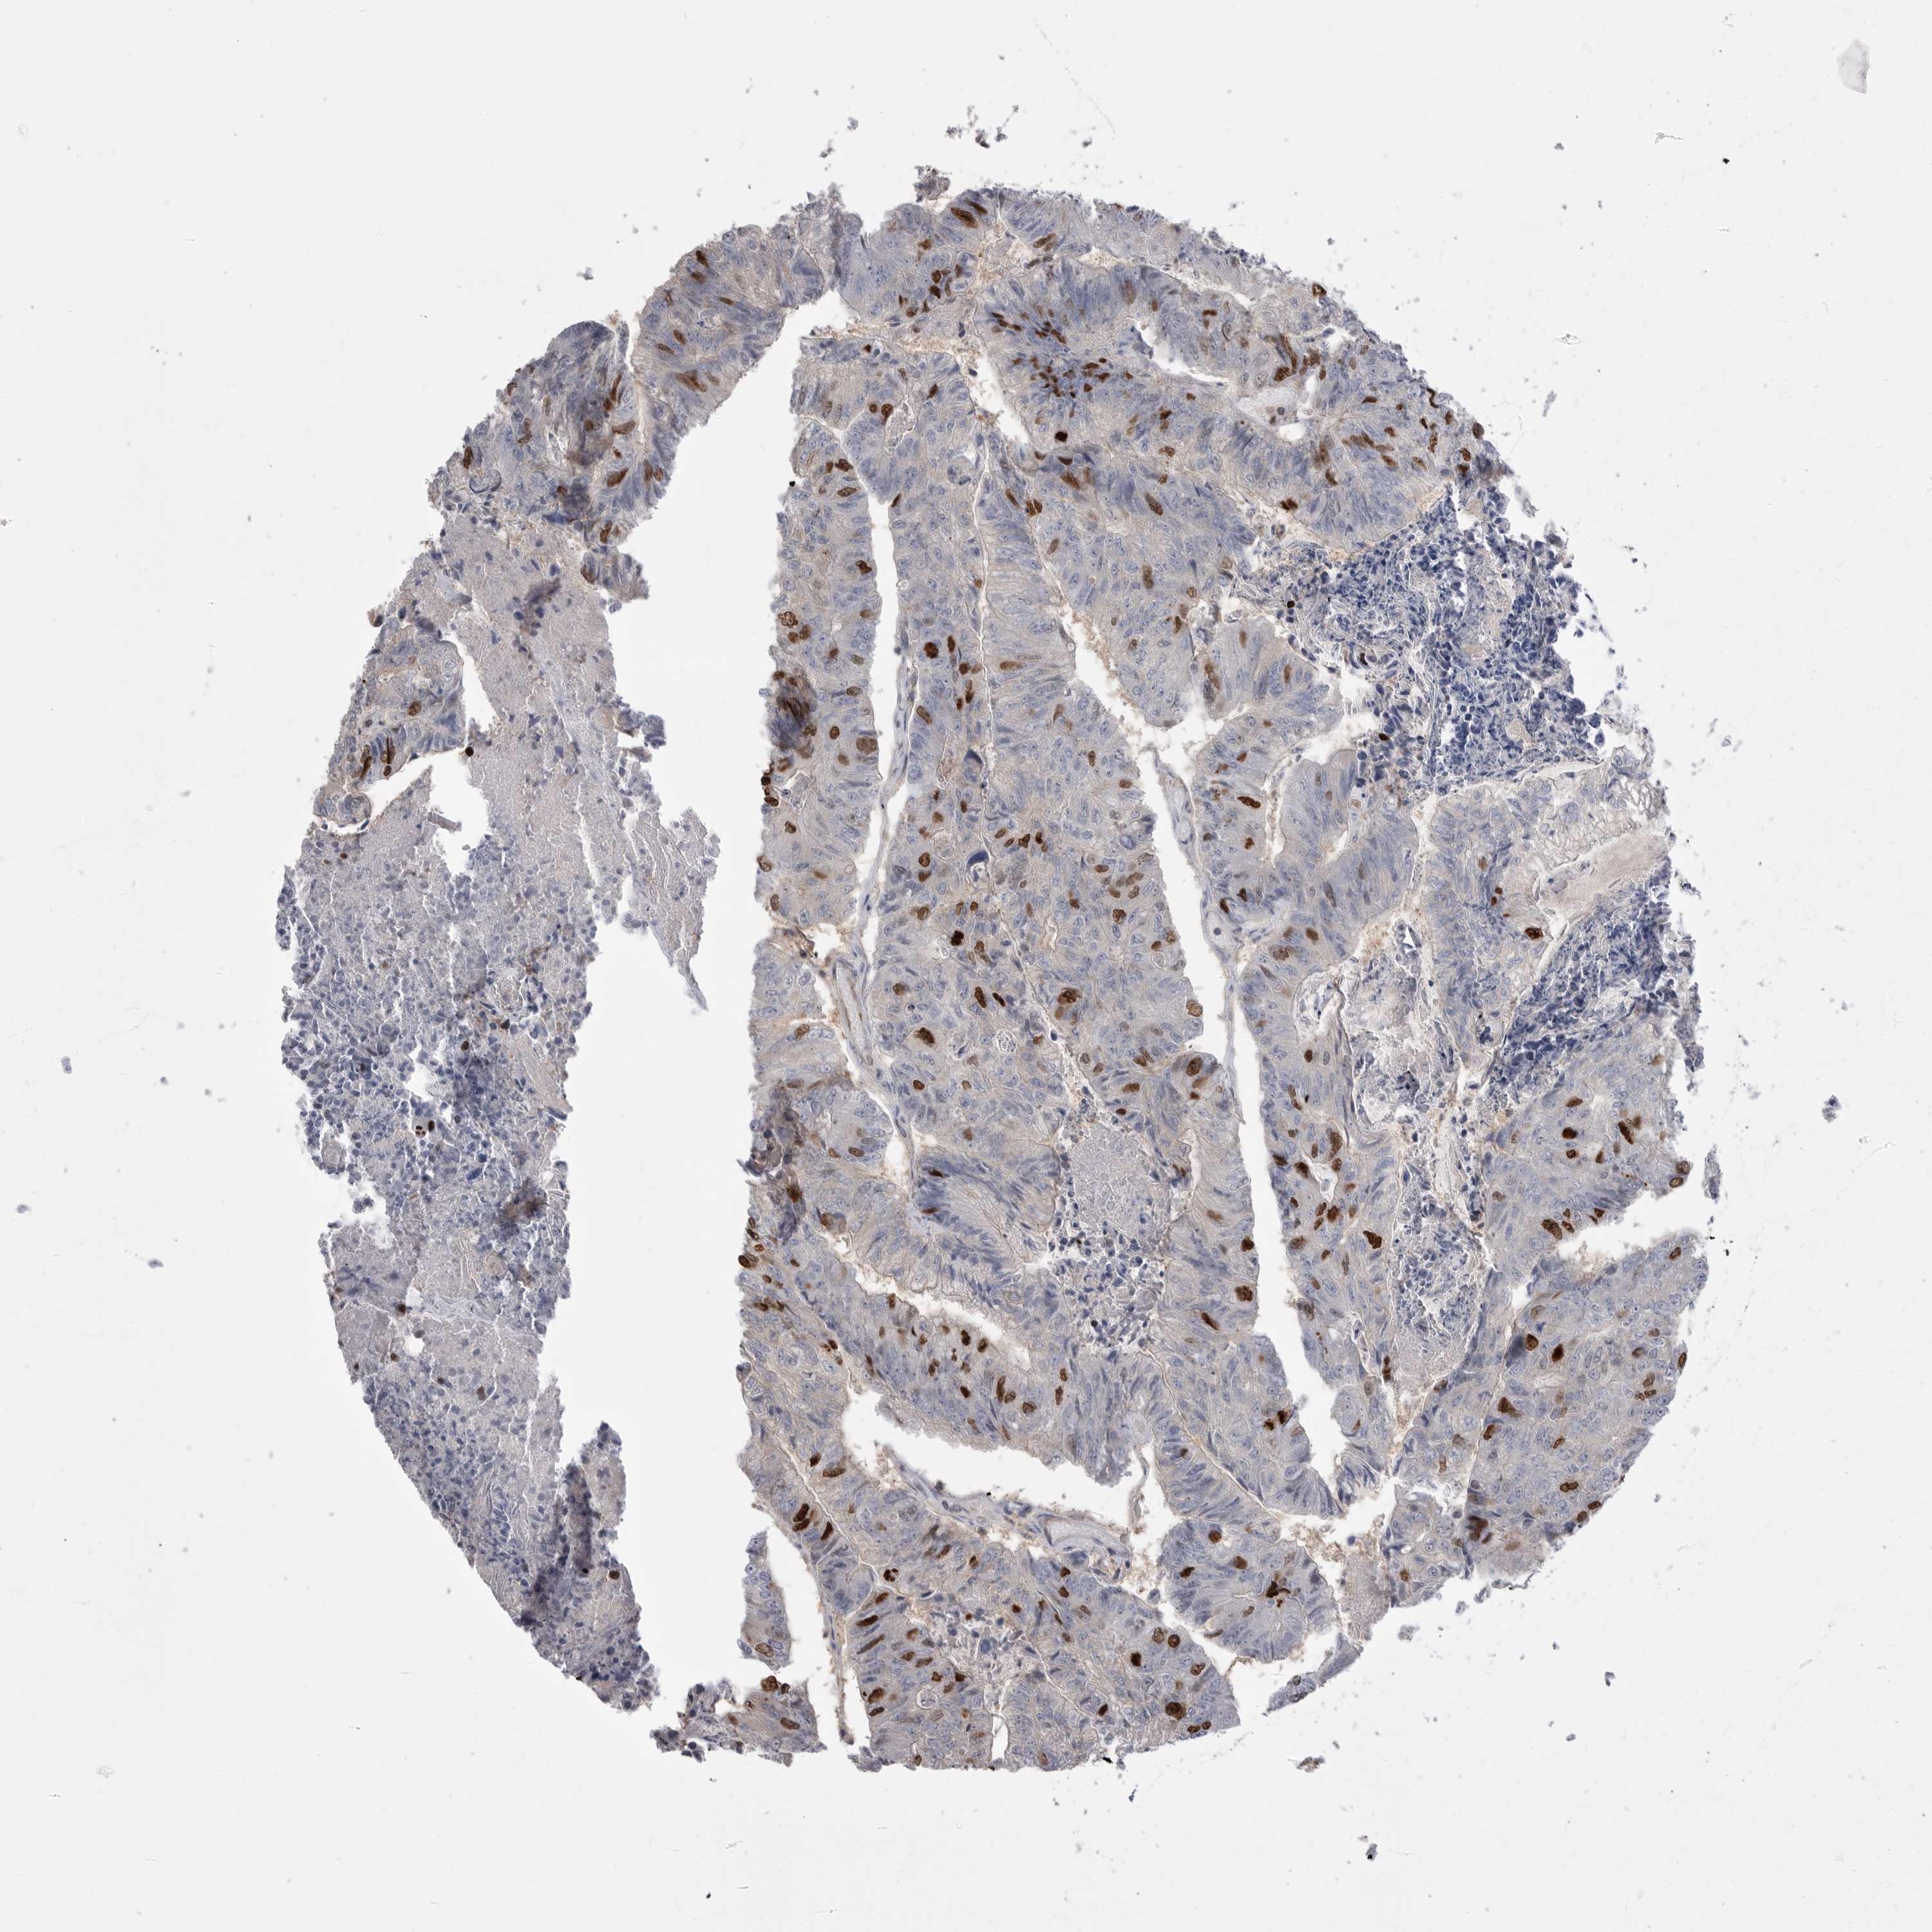

CANCER COLORECTAL CANCER Show tissue menu

ANTIBODIES

AND

VALIDATION